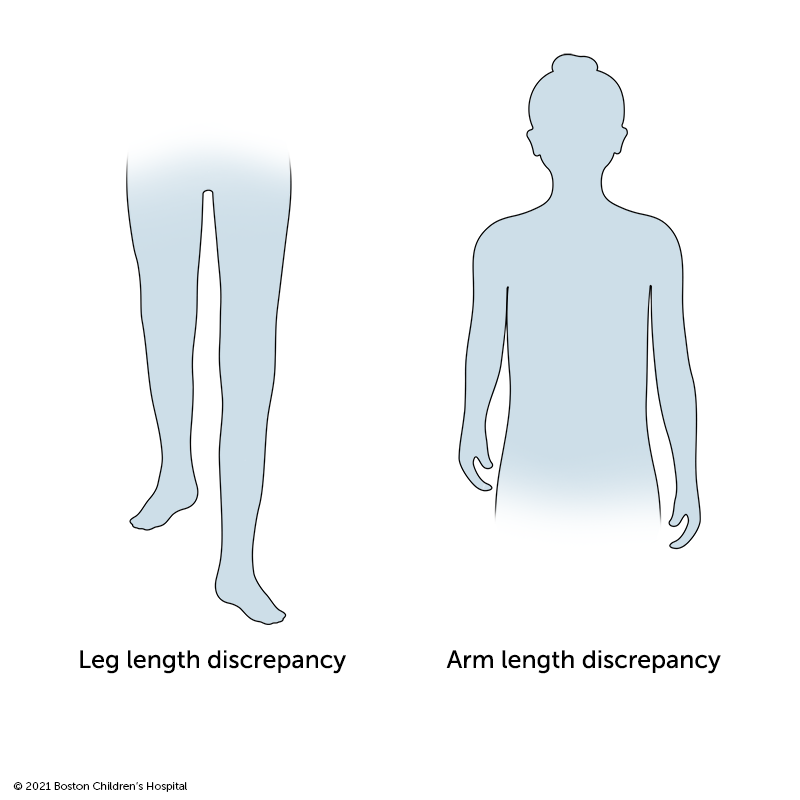

A limb-length discrepancy is when one leg or arm is shorter than the other leg or arm. The difference in length can range from a fraction of an inch to several inches. Some children are born with congenital limb differences that cause their legs or arms to grow at different rates. Other limb-length discrepancies are caused by serious fractures, a fracture that does not heal properly, a bone infection such as osteomyelitis, or bone tumors or bone cysts.

Compared to differing arm lengths, leg-length discrepancies are more likely to affect a child’s daily activities. Legs of two different lengths require children to change their normal posture and walking patterns. Depending on the degree of difference, leg-length disparities can lead to a variety of problems, such as functional scoliosis, and hip, knee, and ankle problems.

Children with mild arm-length discrepancies often adapt well to the difference. However, a difference in arm length of two to three inches or more can interfere with activities of daily life and should be addressed.

The symptoms of a limb-length discrepancy vary widely from child to child based on whether a leg or arm is affected, the degree of difference in length, and the cause of the condition.